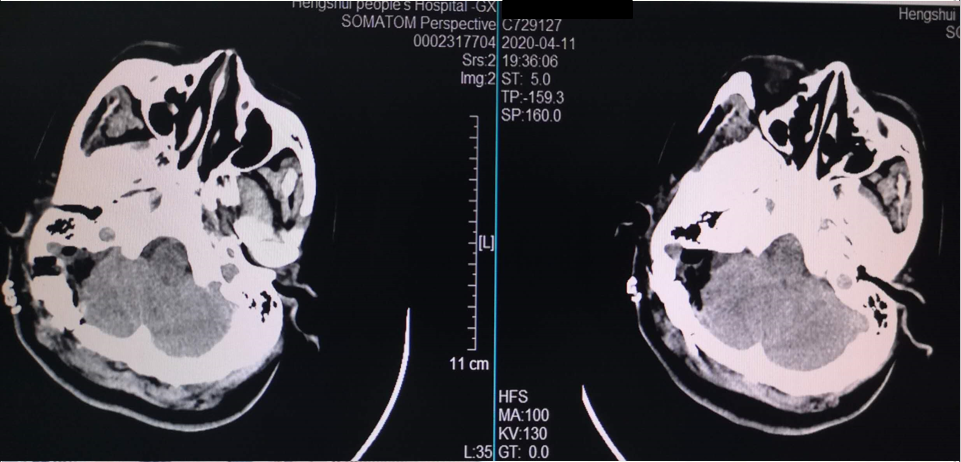

术后复查CT

70岁男性患者。右侧面部疼痛10年,加重半年,既往有糖尿病史20年,高血压史7年。V2和V3区域电击样疼痛。

MRI示:右侧三叉神经区域有粗大基底动脉。